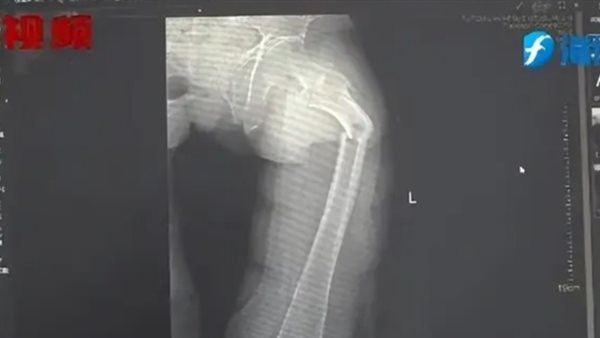

وأظهرت الأشعة السينية أن «السيد يي» قد عانى من كسر في عظم الفخذ، لكن قصته عن السعال لم تكن منطقية ولم يكن هناك أي علامة على وجود أي صدمة جسدية.

نتيجة الأشعة السينية